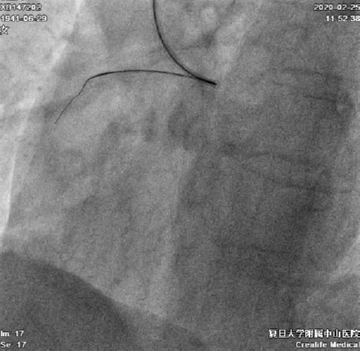

患者右冠异常开口于左冠窦,经左侧桡动脉先后尝试置入7F SAL 0.75SH、1.0SH、EBU 3.5SH、BL 3.25指引导管均无法到达右冠口,最终BL 3.0指引导管成功送至右冠口(图4)

图4